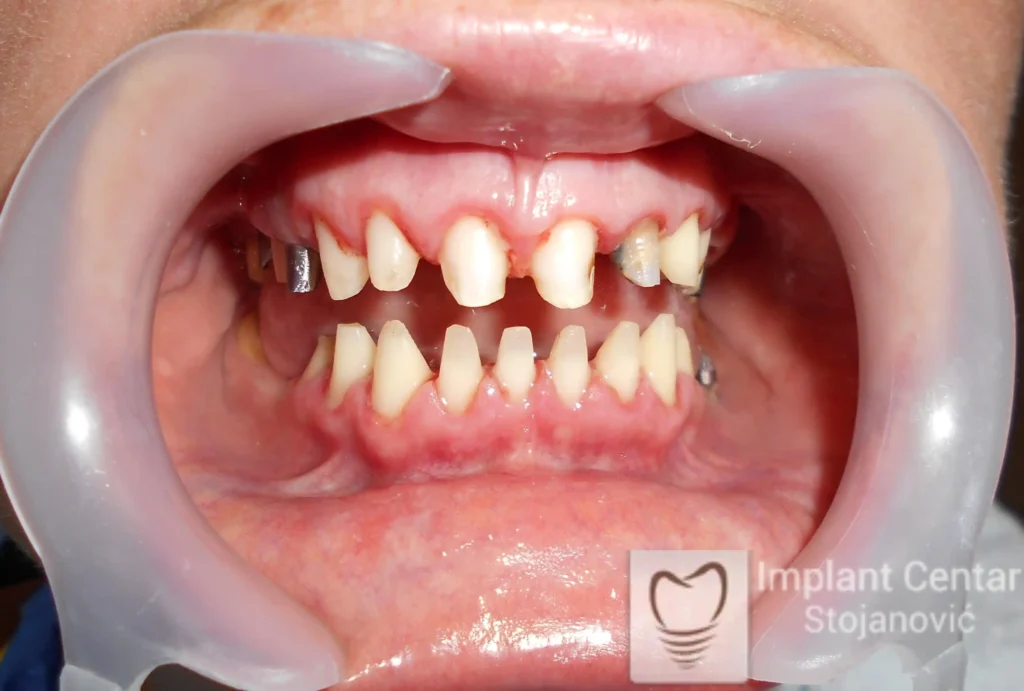

Na slikama 1 i 2 prikazan je klinički izgled pacijenta pre početka terapije. Nakon detaljnog kliničkog pregleda, analize radioloških snimaka, kao i razgovora sa pacijentom o njegovim željama i očekivanjima, izrađen je sveobuhvatan plan terapije. Terapija je podrazumevala vađenje preostalih zuba, ugradnju dentalnih implantata i izradu fiksnog protetskog rada na implantatima.

Tokom perioda osteointegracije, pacijent je bio zbrinut fiksnim privremenim krunicama na implantatima, čime su očuvani estetika i funkcija. Nakon završetka perioda integracije, izrađeni su definitivni cirkonijum-keramički mostovi (slika 6 i 7 ).

Pacijent je izuzetno zadovoljan postignutim rezultatom, jer su u potpunosti vraćeni prirodan izgled osmeha i puna oralna funkcija.